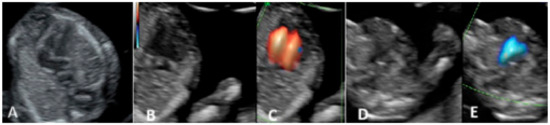

2.2. Second Trimester Scanning and Sections

3.2. Second-Trimester Evaluation